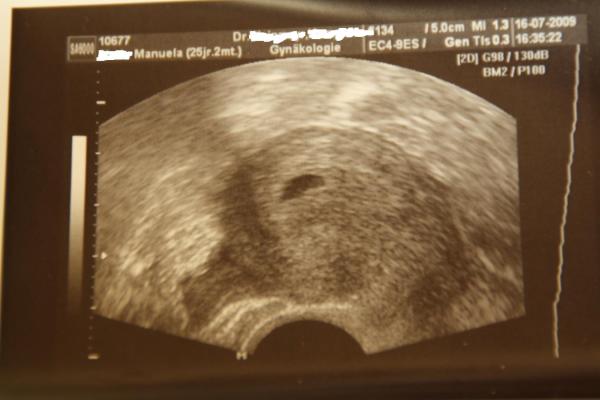

Hallo Mädels, heute war es endlich so weit, ich war beim FA... Hab ein schönes Bildchen mitbekommen (anbei), man sieht die Fruchthöhle (1cm) und einen mini Punkt, das ist wohl der Krümel... Darf heute in 2 Wochen wieder kommen, freu mich schon total drauf. Ich bin glücklich, jetzt check ich irgendwie erst, dass ich wirklich schwanger bin. Ach ja, ET ist der 17.03.2010 vlg Manu (SSW 5+3)

Bild zu Hatte heute 1. FA-Termin - Forum für März - Mamis